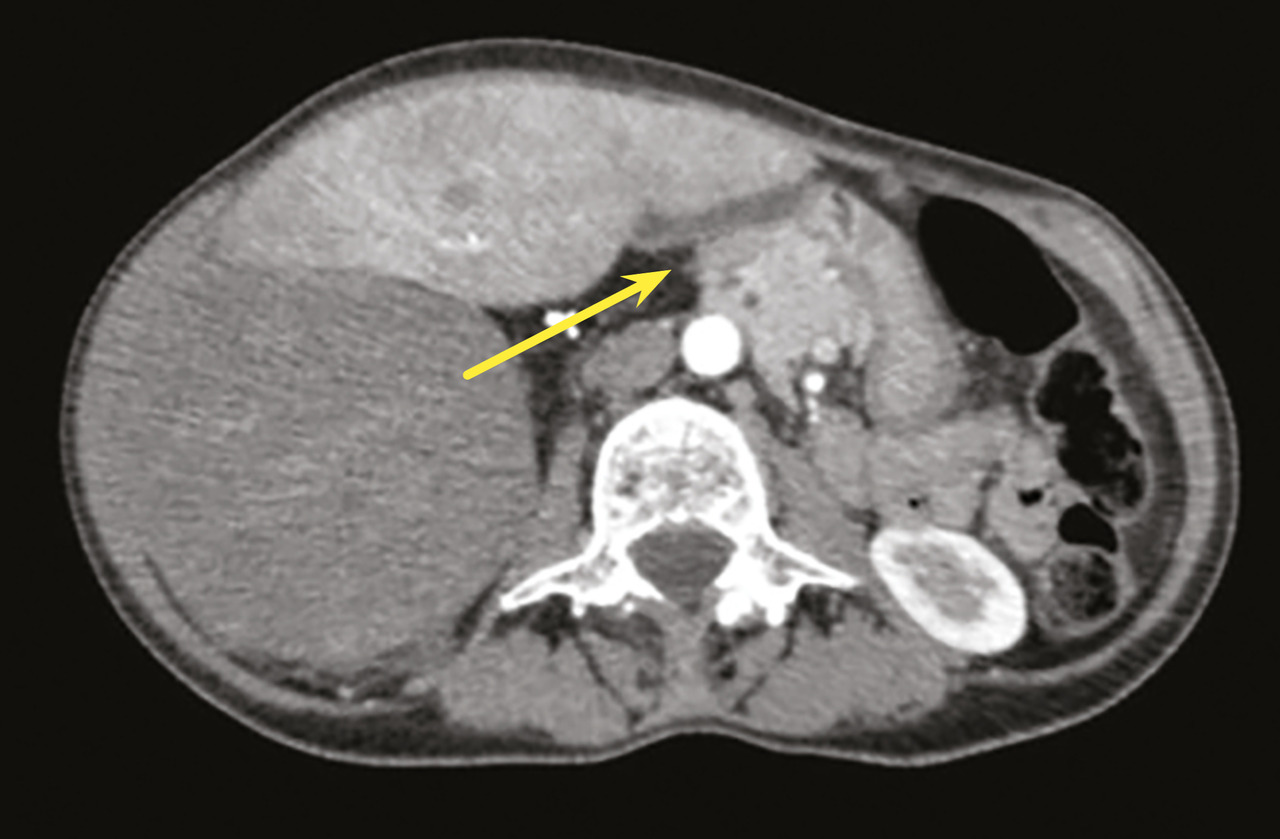

Au niveau abdominal, les signes sont fréquemment une augmentation du périmètre abdominal ou des troubles digestifs ; le patient s’est parfois mis au régime, avec pour conséquence une dénutrition, qui doit être dépistée avant la chirurgie.7 Le scanner abdominal est le premier examen à réaliser. Il convient d’être vigilant à l’égard de l’extension des tumeurs abdominales, en particulier rétropéritonéales, dans les défilés anatomiques (arcade crurale, trous de conjugaison, hiatus œsophagien), source de reliquats macroscopiques.8 De même, la composante bien différenciée (qui ressemble à de la graisse normale) d’un liposarcome rétropéritonéal est très souvent sous-estimée, ce qui peut engendrer des exérèses incomplètes, à l’insu d’un opérateur non spécialisé (fig. 1). Il est essentiel de considérer le déplacement des organes intra-abdominaux pour voir l’ensemble de la tumeur.9 Il est nécessaire de vérifier l’absence d’atteinte osseuse associée, qui modifie la classification diagnostique et donc les modalités thérapeutiques, notamment le choix du chirurgien expert.

Les critères de qualité de la chirurgie des sarcomes rétropéritonéaux sont d’une part une exérèse en un bloc et d’autre part des marges saines sur la plus grande superficie (fig. 2).11 Il ne faut pas faire de biopsie chirurgicale par cœlioscopie ou laparotomie car cela correspond à une effraction tumorale.8,11 Si le patient a été opéré d’emblée sur un diagnostic erroné de tumeur intrapéritonéale (sur une hypothèse de tumeur de l’ovaire, par exemple) et que l’on constate que la tumeur est rétropéritonéale, il vaut mieux refermer et prévoir une biopsie percutanée par voie rétropéritonéale ensuite. Après une exérèse fragmentaire, le patient est exposé à un essaimage péritonéal plus ou moins rapide selon le grade, et une reprise chirurgicale ne modifie pas ce risque.